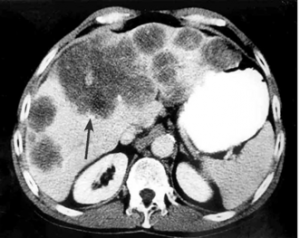

- CT המראה נגעים בכבד. בשאתות קטנות הרגישות של ה- CT ו- US זהה ולכן US משמש לסיקור באוכלוסיות בסיכון גבוה. בעזרת ה- CT ניתן לאתר גם נגעים מחוץ לכבד. ה- CT הספירלי מאפשר לנו לבצע שחזור כלי דם ולהדגים את עושר כלי הדם העוטפים את השאת. ההדגמה ב- CT היא תלת פאזית

- בדרך כלל אין צורך בביופסיה מחטית של הנגע בתנאי שניתן לראות ב- CT מאפיינים קלאסיים ל- HCC. כיוון שה- HCC היא שאת מאוד וסקולרית הרי שהיא "נצבעת" מהר וחזק בשלב ההזרקה ויש שטיפה מהירה בשלב הפורטלי המאוחר (תצלום 30.10-33.10).

| תצלום 30.10: שאת בכבד הנראית ב- CT. מימין HCC הבולטת על פני הכבד. משמאל פגם מילוי בכבד כביטוי לשאת בכבד (החץ מצביע על השאת). | |

|---|---|